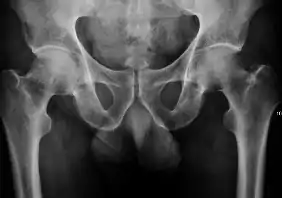

Plain radiography allows us to categorize the hip as normal or dysplastic or with impingement signs (pincer, cam, or a combination of both). Besides these, pathologic processes like osteoarthritis, inflammatory diseases, infection, or tumors can also be identified (Figure 1).[1]

Figure 1.